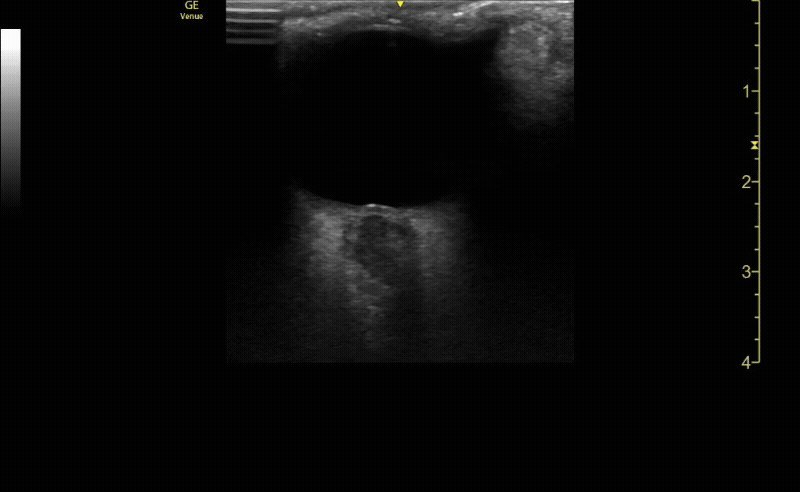

Sagittal (long) view of the right eye. Ensure to scan both right and left for credit.

c/o Victoria Gonzalez